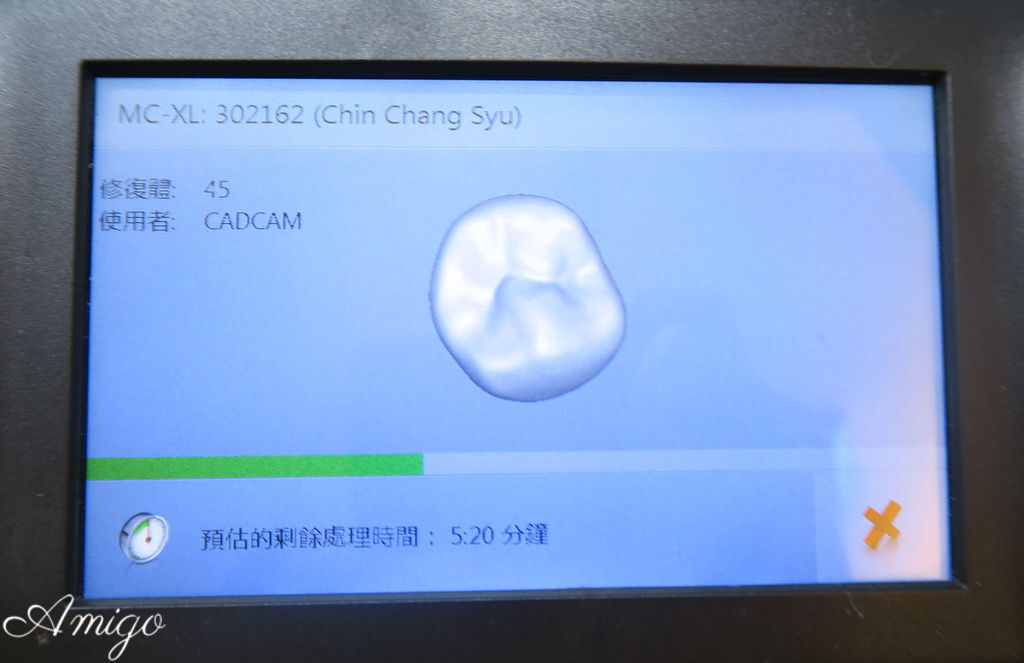

便將假牙資訊傳送到下面這台德國VITA數位研磨機中

接著

將剛才透過比色儀挑選出來的色號瓷塊放入研磨機

醫師及技師根據患者適合的假牙類型((全瓷冠或全鋯冠

判斷假牙要使用乾式或濕式研磨機中

這顆全瓷假牙所搭配的是濕車研磨機

因此在接下來研磨的過程中

會以大量的水柱幫助潤滑打磨

車製所剩餘的時間在螢幕板上顯示

這顆假牙只需要不到十分鐘的時間便可以研磨完成~

速度實在快得驚人!